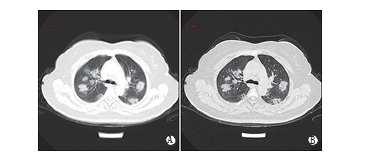

图3 典型CT/X线影像表现(例3)

男性,65岁,发热4 d(38.7℃)。实验室检查,WBC:3.72×109/L(正常),LYMPH:0.90×109/L(减低),CRP:53.0 mg/L(升高), PCT:0.10 ng/ml(升高),肝功能减低,低蛋白血症,轻度贫血。A、B示右肺中叶大片实变和下叶后基底段斑片状实变、内见充气支气管征,3C示左肺下叶外基底段斑片状实变,右侧胸腔少量积液。

图4 不典型CT/X线影像表现(例1)

女性,83岁,发热(最高体温达38.8℃)、咳嗽、畏寒,伴咽痛、干咳1周,胸闷和气短加重1周。实验室检查,WBC:4.6×109/L (正常),Neu%:65.8(正常),LYMPH%:19.9(减低)。A、B示双肺弥漫性小叶间隔增厚形成网格影、支气管壁增厚、左肺下叶片状实 变,4C胸片示双肺弥漫网格影、左肺为著。